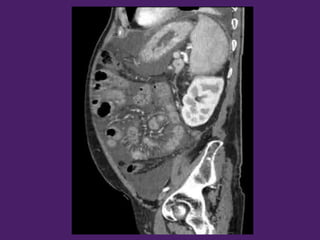

Hígado

Ángulo esplénico del

colon

Ángulo hepático

del colon Colon

transverso

Lóbulo derecho

del hígado

Lóbulo izquierdo

Fundus

gástrico

Vesícula

biliar

Antro del

estómago

Vena renal Izquierda

Arteria mesentérica

superior

Tronco

celíaco

Vena cava Inferior

ascendente